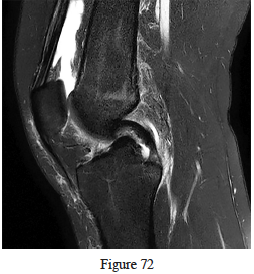

72. Figure 72 is the MR image of a torn structure consisting primarily of which collagen type?